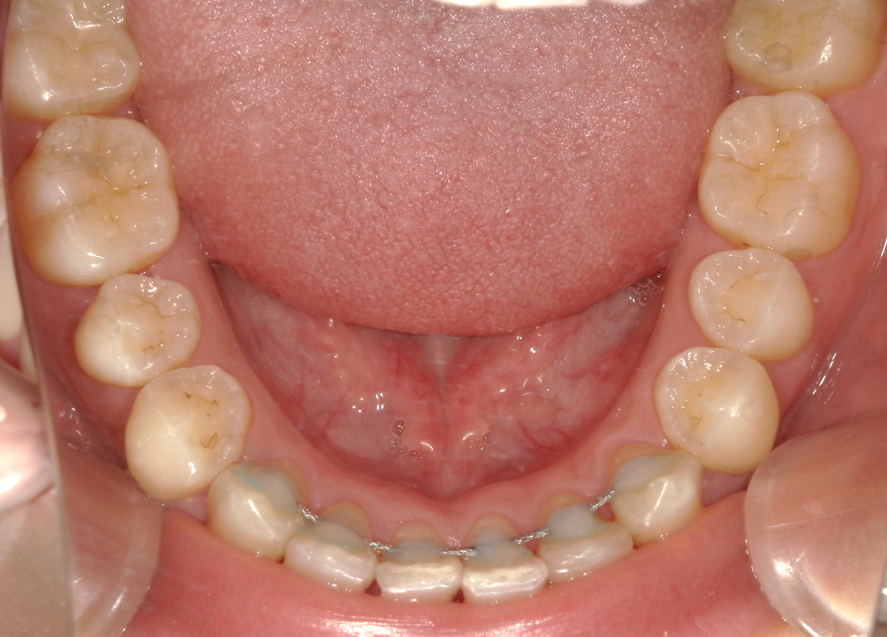

術前⑤:下顎口腔内

|

| 主訴 | 歯並びを良くしたい |

|---|---|

| 診断名・主な症状 | 上下顎叢生。クロスバイト |

| 年齢 | 10 代 |

| 治療に用いた主な装置 | 全顎ブラケットを装着。途中バイトアップしてクロスバイトの改善 |

| 抜歯有無・抜歯部位 | なし |

| 治療期間 | 1 年 5 か月 |

| 治療費用 | 70 万円 |

| リスク・副作用 | 後戻り防止の為、将来、親知らずの抜歯をする |